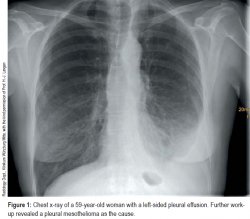

I had also high fever, rib pain, back pain. cxr and ct thorax revealed a right sided fluid collection reported by radiology as loculated pleural effusion along with bilateral layering pleural fluid. pleural effusions in children most commonly are infectious (50% to 70% parapneumonic effusion); pleural effusions are characterized on ct by attenuation values between those of water (0 hounsfield units hu) and soft tissue (approximately 100 hu), typically in the order of 10 to 20 hu. We reviewed patients that received alteplase for persistent loculated pleural fluid collections after simple tube drainage between july 01, 2007 and november 01, 2012. Albeit methodologies were different, the predictive value of these indicators was confirmed in our study, where radiologically small effusions and signs of loculation on cxr were associated with inaccurate puncture site. Treatment may fail if the catheter is not placed optimally within the loculation or if the fluid is hemorrhagic or fibrinous. If the lesion has a smooth interface with the thoracic wall, first check whether there is a pleural effusion or whether the ribs are destroyed. There is a large left pleural effusion obscuring the lower half of the left hemi thorax. Ultrasound is superior to ct in demonstrating septae in the pleural space. Hence, all thromboembolic diseases, including stroke patients who receiving anticoagulant therapy and sudden appearance of pleural effusion in cxr, hemothorax should always be fi rst suspicion. Mesothelioma is the commonest primary pleural malignancy and typically presents with chest pain, pleural effusion, and dyspnea. More than one half of these massive pleural effusions are caused by malignancy;